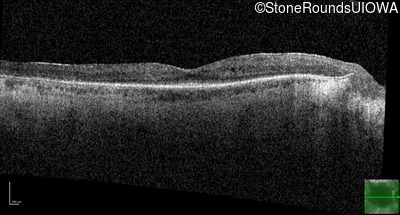

Optical Coherence Tomography - Left - 20/40 +1

Exemplar / OCT Stack

OCT Stack